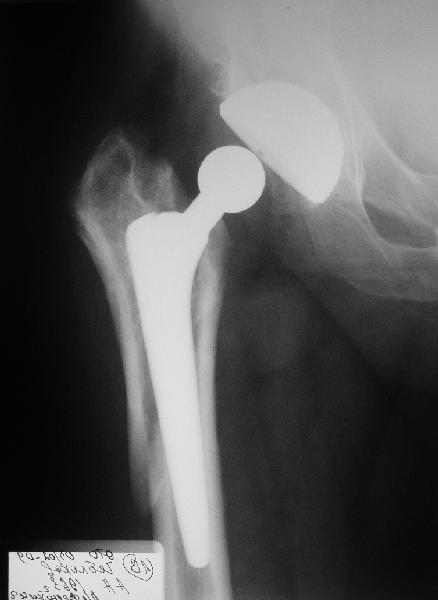

Мужчине 1963 г.р. в октябре прошлого года в Кургане сделано эндопротезирование правого тазобедренного сустава (последствия перелома шейки бедра) бесцементным протезом Cerafit.

Все было благополучно, пациент уже ходил без трости, когда в начале января 2009 упал на улице на правый бок.

Госпиталирован по месту жительства (МСЧ г. Новоуральск). Уложен на скелетное вытяжение. На снимках от 3 февраля видно миграцию ножки в дистальном направлении, она явно нестабильна. В нашей больнице вряд ли что-то удастся сделать. Сопутствующих заболеваний нет. Хотелось бы получить совет по тактике. Если нужно ревизионное протезирование, куда лучше пациента направить? Спасибо.

У пациента перипротезный перелом бедра тип 2Б по ванкуверской классификации.